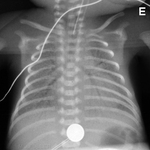

Avaliação da cianose neonatal

Fístula traqueoesofágica: sonda orogástrica torcida no esôfago

Do acervo de Ponthenkandath Sasidharan, MD; usado com permissão